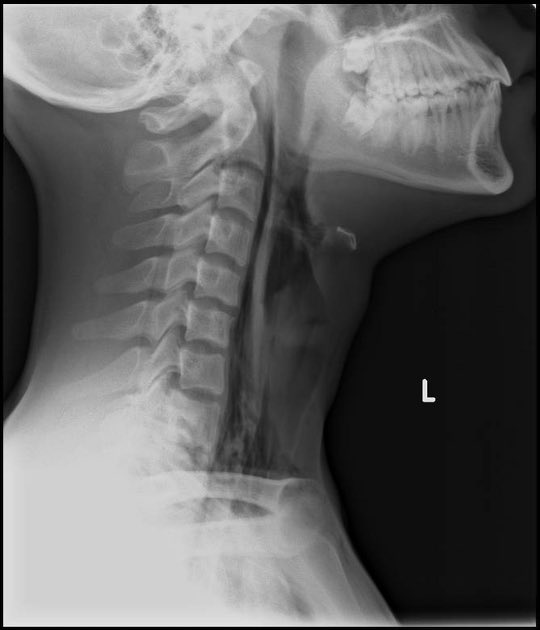

Patient c/o unable to speak and had a sore throat. Was swallowing a pill and felt that it was stuck in his throat.

X-ray showing :

Extensive pre vertebral soft tissue gas with extension into bony spinal canal.

These findings are highly suggesting : oesophageal perforation #EM